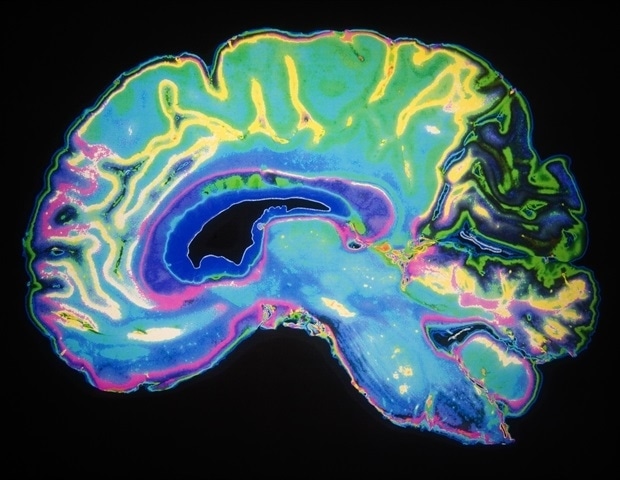

Используя сочетание поведенческих экспериментов, записей мозга (ЭЭГ), стимуляции мозга и компьютерного моделирования с участием 106 участников, исследователи из Каролинского института исследовали, как мозг объединяет визуальные и тактильные сигналы, чтобы создать ощущение принадлежности части тела себе — феномен, известный как чувство владения телом. Их эксперименты показали, что частота альфа-волн в теменной коре головного мозга, области мозга, которая обрабатывает сенсорную информацию от тела, определяет, насколько точно мы воспринимаем свое тело как свое собственное.

Чтобы проверить, вызывает ли альфа-частота непосредственно эти перцептивные эффекты, исследователи использовали неинвазивную электрическую стимуляцию мозга, чтобы немного ускорить или замедлить альфа-волны участников. Результаты показали, что такая регулировка альфа-частоты также изменила то, насколько точно люди ощущали владение телом и насколько точно они воспринимали визуальные и тактильные стимулы одновременно. Вычислительные модели показали, что альфа-частота влияет на то, насколько точно мозг определяет время сенсорных сигналов, а это означает, что эти мозговые волны регулируют временную точность восприятия и тем самым помогают формировать наше ощущение телесного «я».